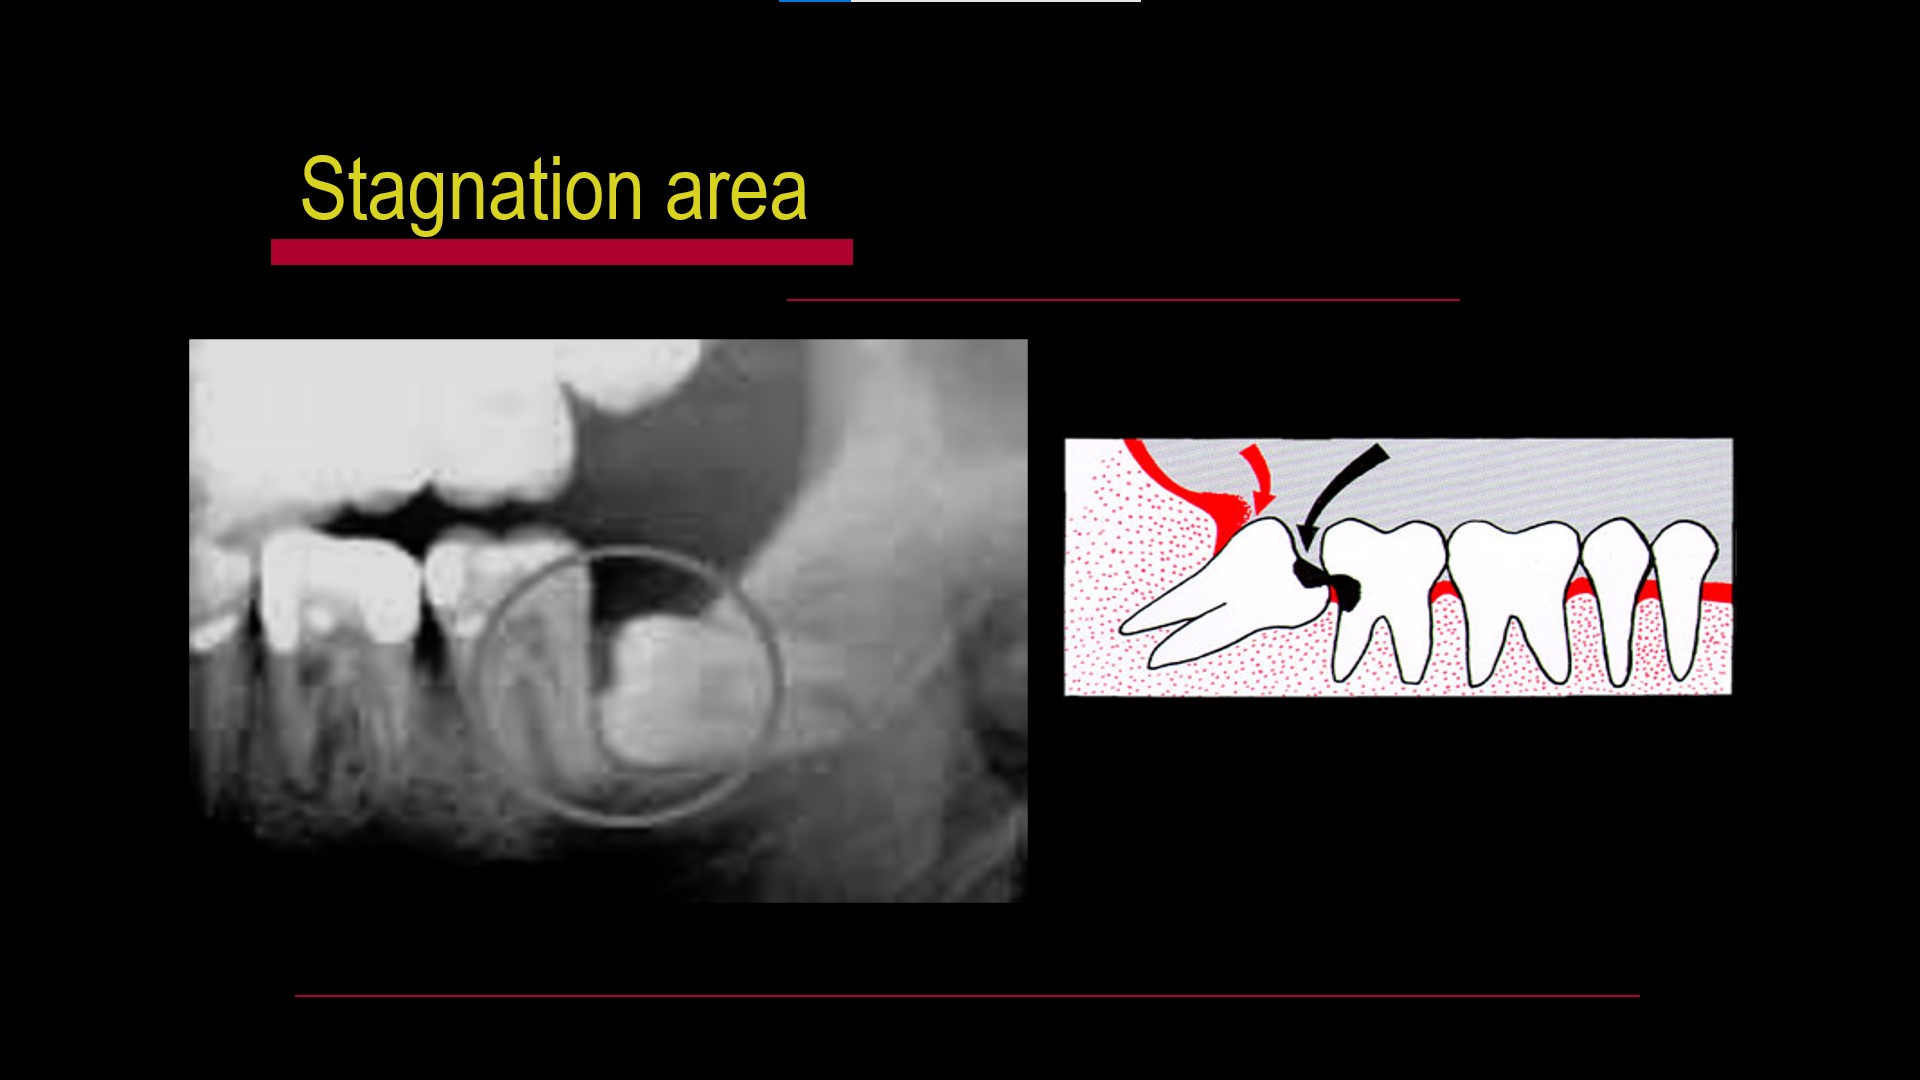

Impacted teeth

Pericoronitis